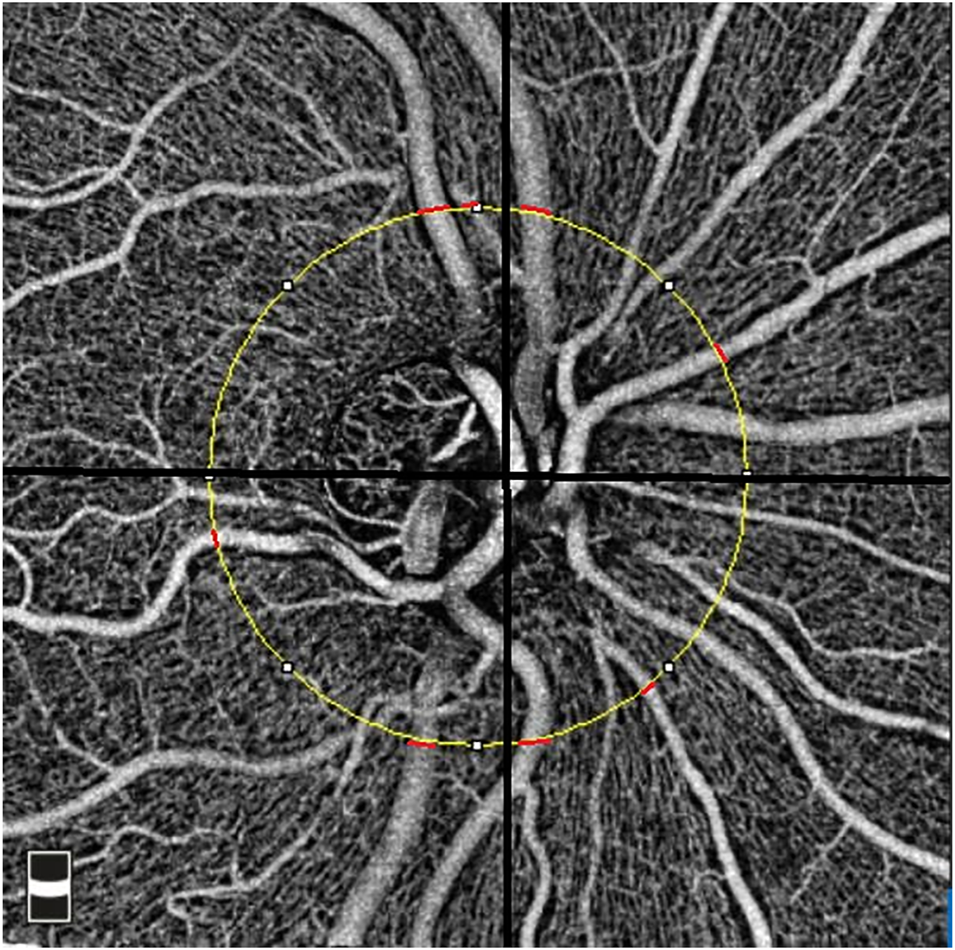

Retinal Vessel Caliber Measurement

The optic nerve head (ONH) cube scan at 4.5 mm × 4.5 mm field of view was acquired. We analyzed the ONH cube scan at the retinal nerve fiber layer segmented automatically by OCTA software to measure the peripapillary vessel diameter. A circle with a diameter of 3.4 mm was centered on the ONH. For each peripapillary quadrant, the largest diameter vein and artery were marked. Two independent, trained ophthalmologists measured the width of the marked vessels at the border of the previously fitted 3.4-mm circle (Figure 2). For this purpose, an image magnification of 200× was selected. The graders selected the most appropriate image brightness and contrast to detect the borders of the vessels. The border of the vessels was manually determined using an edge-based approach (Bhargava et al., 2012).

FIGURE 2

Measurement of the peripapillary vessel caliber in the 4.5 × 4.5 mm optical coherence tomography angiography image. The yellow circle represents a 3.4-mm circle centered on the disc. The location of the measurements was shown using red lines for peripapillary quadrants.